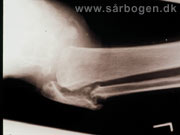

Charcot i ankel (rtg...